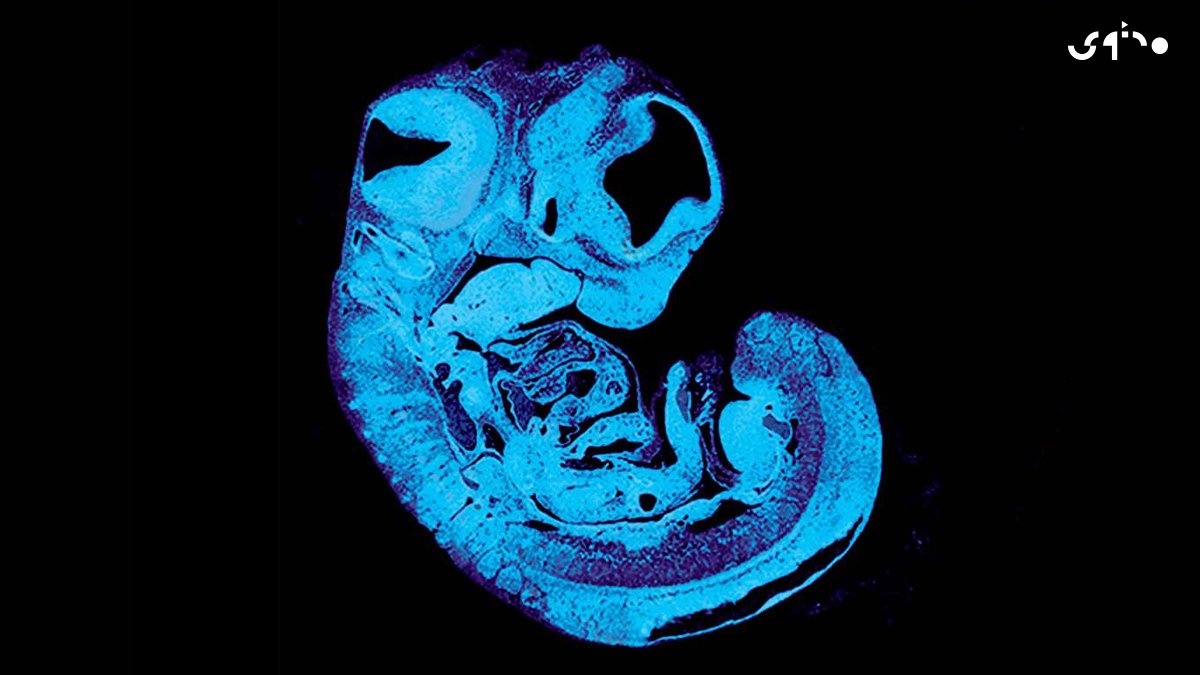

أجرى علماء من جامعة "كامبريدج" دراسة على فئران معدلة وراثياً نشرت في مجلة "Development Cell" تشير إلى أن الجنين يرسل إشارة تسمى بـ"IGF2"عبر الحبل السري للحث على التمدد الصحيح للأوعية الدموية داخل المشيمة للسماح بمرور المزيد من العناصر الغذائية من الأم إلى الجنين

المثير في الدراسة أن جينات الأب تدفع إلى أكبر تمدد ممكن لهذه الأوعية بغية الحصول على أكبر قدر ممكن من الغذاء فيما تقاوم جينات الأم في محاولات التمدد هذه وتحد من تمدد الأوعية الدموية وتعمل على إبطاء المدخول الغذائي

تعتبر هذه المعركة بين الجنسين على مستوى الجينوم مفيدة للجنين لأنها تحقق التوازن في نموه.. أما الدراسة فستساعد في تفسير سبب ضعف نمو بعض الأجنة في الرحم وانخفاض نمو الأوعية الدموية لديهم كما ستسمح بفهم أفضل لكيفية تواصل الجنين والمشيمة والأم مع بعضهم البعض أثناء الحمل

ستؤدي الدراسة أيضاً إلى قياس مستويات إشارة "IGF2" لدى الجنين بما يسمح بإيجاد طرق لاستخدام أدوية تدعم هذه المستويات وبما يعزز النمو الطبيعي للأوعية الدموية في المشيمة